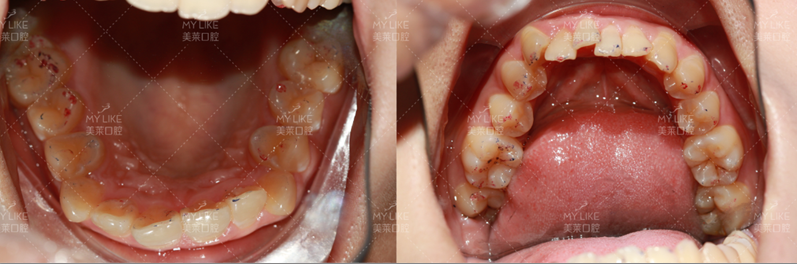

成年人的生长发育虽然已经结束,但并不能说就一定过了黄金矫正期。在现代口腔正畸治疗中,成年人已经成为矫治的一大群体。

虽然成人颌骨改建及牙齿移动速度较儿童慢,但是,由于成人合作程度高,治疗目标明确,受生长发育等不确定因素影响小,一样可以取得非常好的治疗效果。现在有适合成人的“美观矫治器”,如陶瓷托槽、隐形矫治器、舌侧矫治器等,更加美观和隐蔽,但是费用也较高。

原则上来讲,只要牙周健康,成人也可以进行正畸治疗。但由于成人身体状况的特殊性,正畸采用的设计有严格的原则,比如小范围牙移动、后牙咬合关系的考虑、美观和功能的评价和平衡,这些都和儿童期的治疗有所不同。当你考虑进行牙齿矫正时,应请口腔正畸医生进行检查和评估。